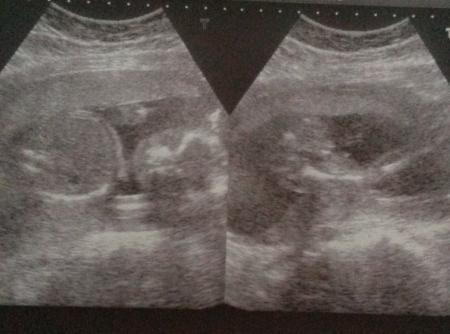

Hallo ihr lieben war gestern beim FA bin in der 20ssw und kann rechts im Bild leider überhaupt nichts erkennen was es darstellen soll könnt ihr mir helfen? LG

Halli hallo. Sieht aus wie Femur ( Oberschenkelknochen), der wird benötigt um FL ( Länge des Kindes= 7* FL) zu bestimmen. Danach kommt der Unterschenkel ( rechts) und dann Fuß. LG